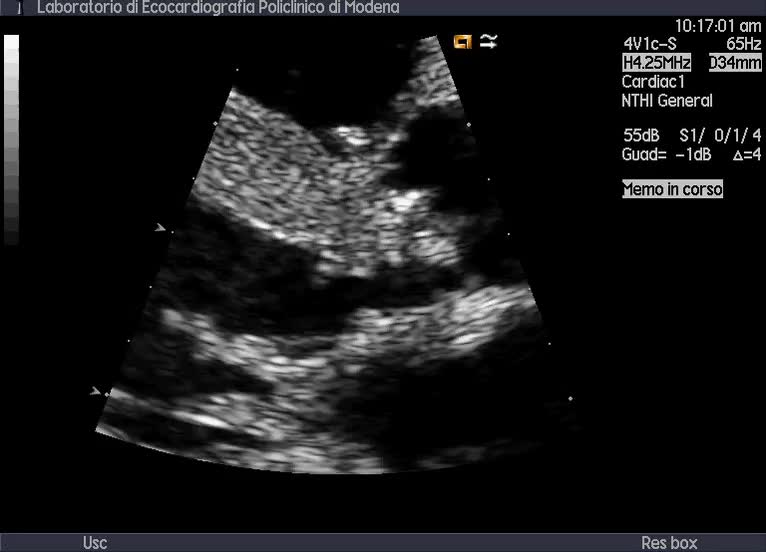

Titolo:

Endocardite su derivazione ventricolo-atriale destra

Autore:

Andrea Barbieri